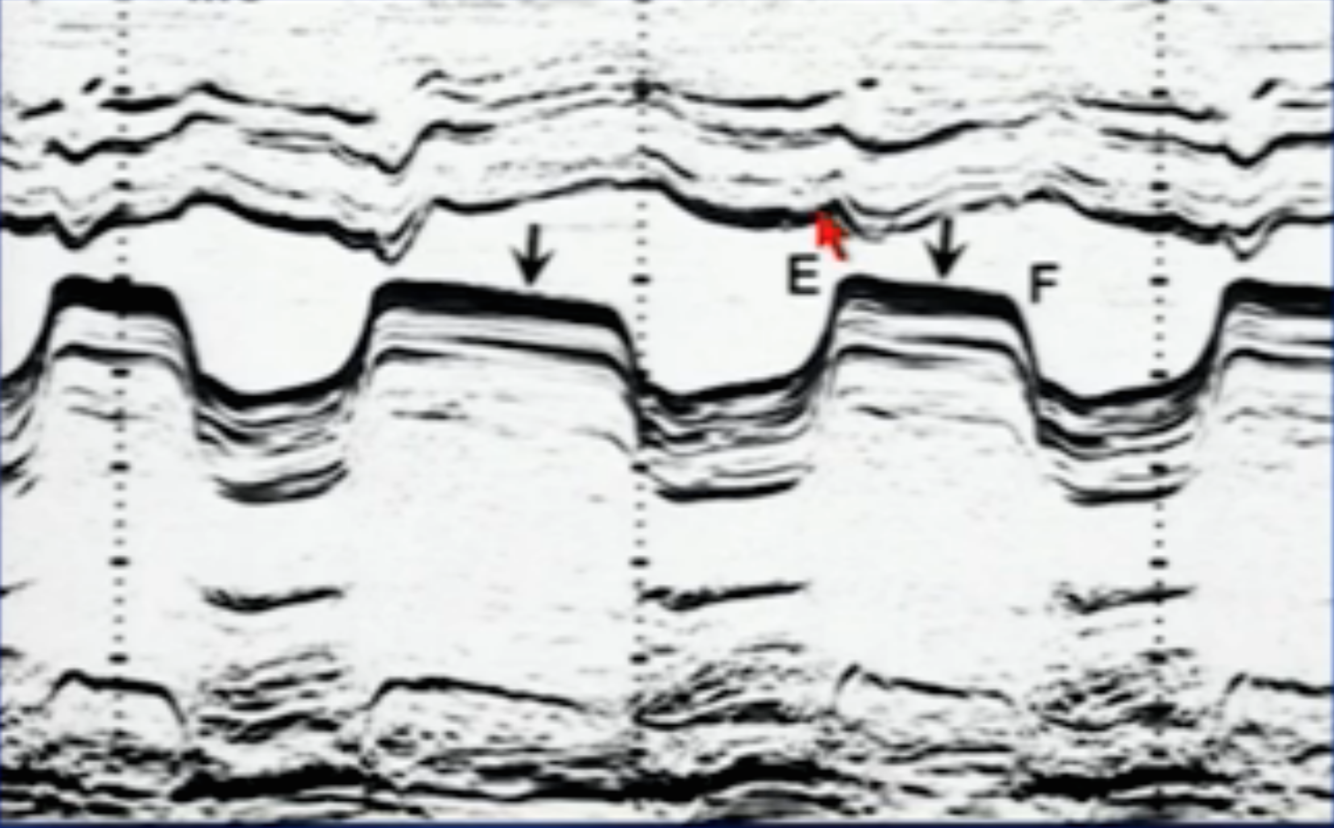

Describe each letter of this MV M-Mode

E- early diastole/rapid filling

A- atrial contraction

F- diastasis onset

C- Closure of MV

D- Opening of MV

Diagnosis

MS

(reduced/loss of the E-F slope of MV M-mode and fish mouth/diastolic anterior motion of posterior leaflet)